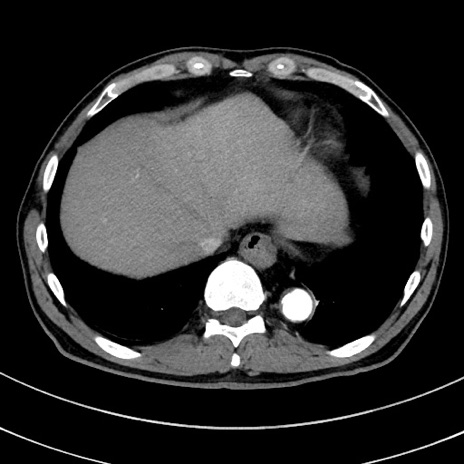

冠状断像

【症例】 60歳代男性

【主訴】 黒色吐物

【現病歴】 4日前から嘔気自覚、2日前の朝食後にも嘔気あり、自分で手で嘔吐反射起こし嘔吐したところ血が混ざっていたため受診。

【既往歴】 5年前汎発性腹膜炎を伴う急性虫垂炎で手術、高血圧、前立腺肥大症、高脂血症

【身体所見】 腹部正中に手術癩痕あり 腹部平坦・軟圧痛なし膨満感あり

【データ】WBC 8400、CRP 4.54